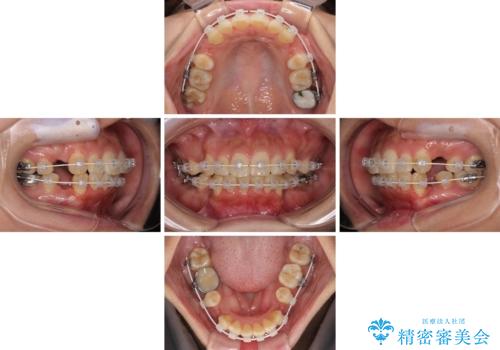

- 審美装置

- 1年7ヶ月

- 10-30回